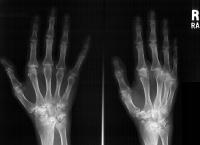

Clinical Example: Rheumatoid arthritis with DRUJ and radiocarpal involvement

Rheumatoid arthritis has many forms of presentation. This patient has bilateral severe radiocarpal and distal radioulnar joint involvement, with relative sparing of the metacarpophalangeal and interphalangeal joints.

Note the spontaneous radiolunate fusion.